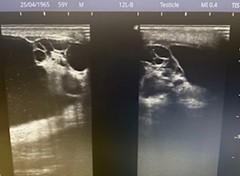

Caso 2: En escroto izquierdo imagen anecoica correspondiente a hidrocele a tensión, con coexistencia de trabeculaciones y loculaciones en el interior de hidrocele.

Caso 2: se solicita ecografía reglada.